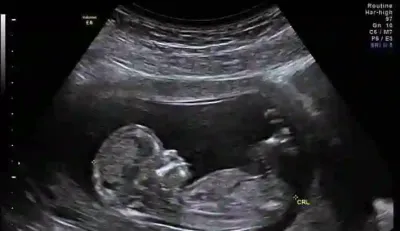

مهم‌ترین سونوگرافی در بارداری یا همان غربالگری دوم

غربالگری دو یا سونوگرافی آنومالی که در هفته 18 تا 22 بارداری باید انجام شود، مهم ترین سونوگرافی بارداری است. چون در آن، تفری